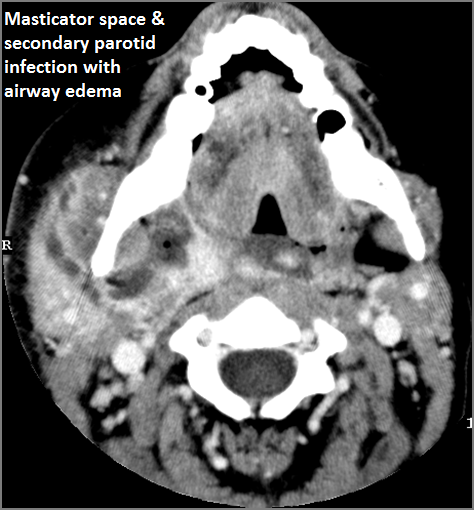

Info Images Findings Impression Reco/Acuity Case Images View Images / Launch Visage Case Notes History 80-year old female in the ICU with acutely swollen right neck. Evaluate for neck hemorrhage. Exam Non-contrast-enhanced CT of the head and maxillofacial region. Prior Study None Dicom View Reference Material

Section 1 Submit Findings Case019 Findings General There is excessive enhancement, edema and/or fluid collection involving the superficial fascia or subcutaneous fat and skin. Yes No There is excessive enhancement, edema and/or fluid collections within or surrounding the mandible/maxilla (dental or sinonasal related), pharynx, parapharyngeal space, buccal space, masticator space, floor of the mouth or neck that would be an alternate explanation for the patient’s symptoms. Yes No There is significant secondary airway encroachment present. Yes No Parotid Glands The parotid glands are enlarged and/or show abnormal enhancement. Yes No There are intraglandular parotid cysts and/or sialocoeles. Yes No There is a developing abscess within the parotid gland. Yes No The parotid ducts and/or intraglandular ductal systems are dilated and/or with evidence of intraductal stones other causes of obstruction. Yes No There is edema (cellulitis) and/or abscess within the fat surrounding the parotid gland and/or of the masticator space or other adjacent spaces. Yes No The retromandibular and the facial veins are abnormal. Yes No There are abnormalities along the course of the facial nerve. Yes No The parotid, retromastoid, subocciptal and posterior neck lymph nodes are abnormal by imaging criteria. Yes No Submandibular glands The submandibular glands are enlarged and/or show abnormal enhancement. Yes No There are intraglandular submandibular cysts and/or sialocoeles. Yes No There is a developing abscess within the submandibular gland. Yes No The submandibular ducts and/or intraglandular ductal systems are dilated and/or with evidence of intraductal stones other causes of obstruction. Yes No There is edema (cellulitis) and/or abscess within the fat surrounding the submandibular gland and/or of the submandibular, sublingual or other adjacent spaces. Yes No The submandibular (Level 1) lymph nodes are abnormal by imaging criteria. Yes No Sublingual glands The sublingual glands are enlarged and/or show abnormal enhancement. Yes No There is edema or abscess within the sublingual space/floor of the mouth. Yes No Other Lymph Node Groups The other cervical (Levels 2-6), supraclavicular and/or retropharyngeal lymph nodes are abnormal by imaging criteria. Yes No Other findings The lacrimal glands are enlarged and/or enhance abnormally. Yes No There is evidence of thrombus, thrombophlebitis or other occlusive or inflammatory process of the jugular vein or smaller venous tributaries. Yes No There is evidence of thrombus, inflammation of the common, external or internal carotid artery. Yes No There is evidence of active extravasation or a contained leakage from an arterial source. Yes No Other significant abnormal findings are present. Yes No